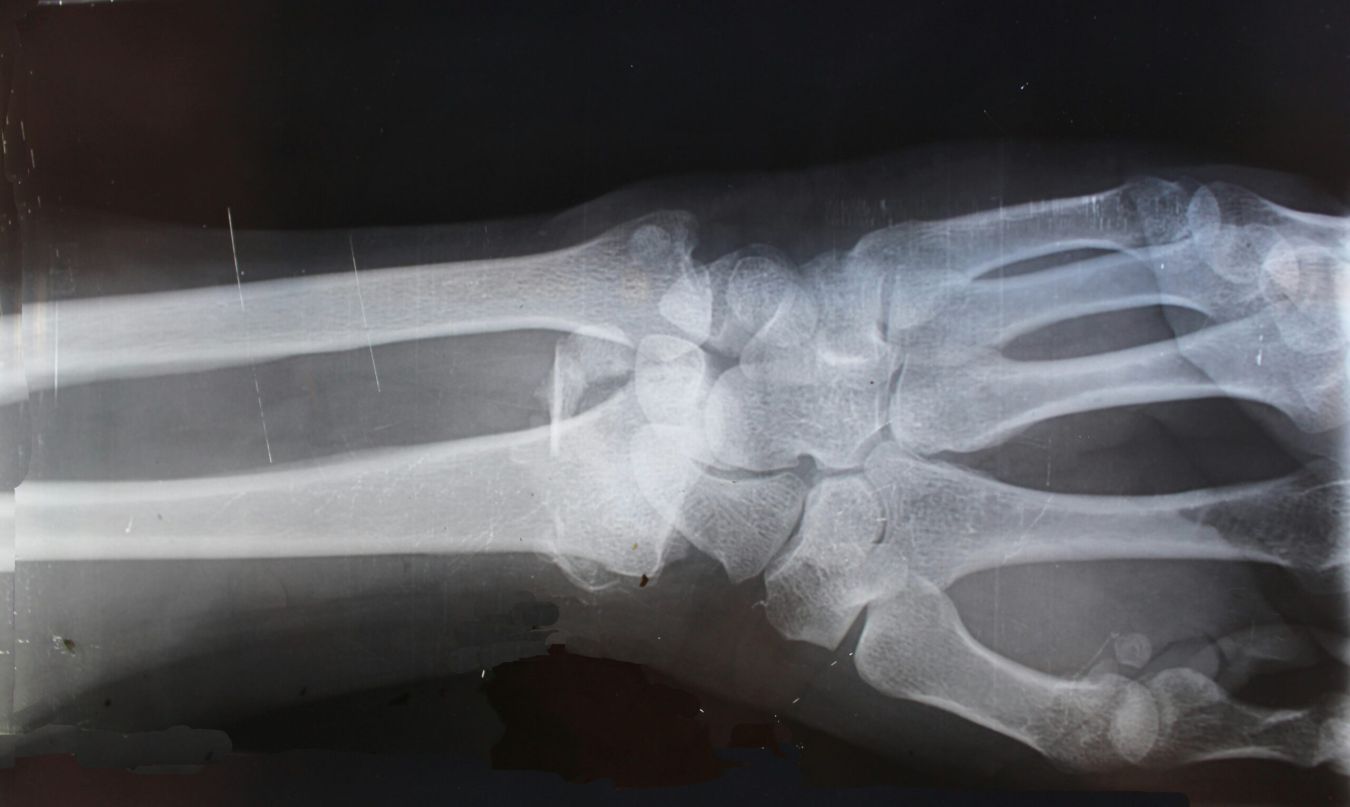

Heeft u misschien een botbreuk aan arm of been? Dan is de kans groot dat uw huisarts of Huisartsenspoedpost Gelderse Vallei in Ede u doorverwijst naar Ziekenhuis Gelderse Vallei. Vanaf maandag 15 december krijgt u daar sneller uitsluitsel of uw arm of been gebroken is. Ziekenhuis Gelderse Vallei neemt dan ook voor aanvragen van huisartsen de AI-tool Gleamer Bone View in gebruik. Deze tool helpt bij het beoordelen van breuken. Als er twijfel is over de breuk, helpt Gleamer om sneller duidelijkheid te geven.

Na het maken van de röntgenfoto bij de afdeling radiologie in ons ziekenhuis, wordt de foto beoordeeld door Gleamer. Gleamer werkt snel en vrijwel foutloos. Voor extra zekerheid beoordeelt een radioloog de volgende werkdag de gemaakte foto’s voor een definitief oordeel. Als de radioloog iets anders ziet dan Gleamer, neemt hij binnen 24 uur contact op met de huisartsenspoedpost of de aanvragende huisarts.